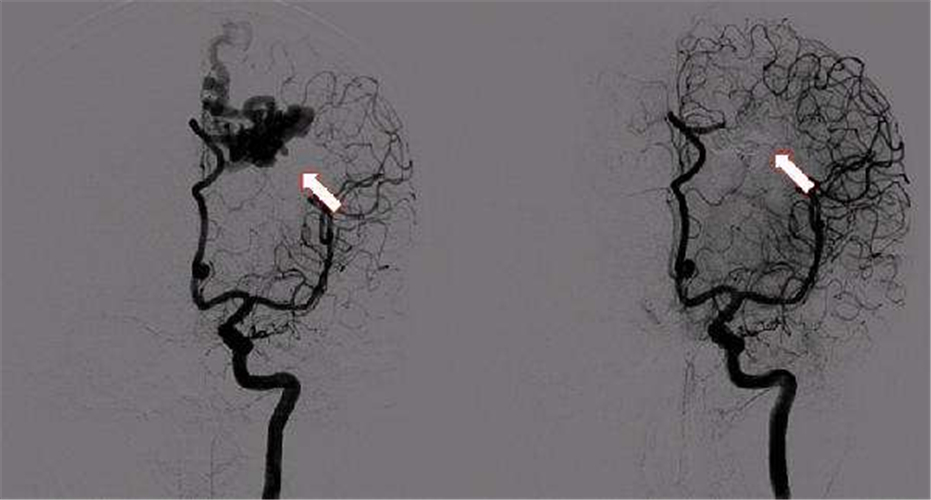

椎基底動脈供血不足導致腦供血不足

一過性腦供血不足檢查

腦供血不足血管造影